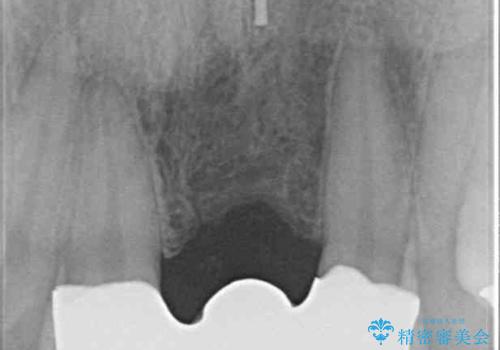

- 接着タイプの前歯のブリッジが不自然であるとのことで来院された患者様です。

欠損部の歯肉が窪んでいるため、歯肉移植により形態を改善し、オールセラミックブリッジにて補綴することとしました。

事前に装着されていた接着タイプのブリッジは、歯の切削量が少ない反面、接着界面から虫歯が進行しやすく、脱落リスクが高くなるというデメリットがあります。